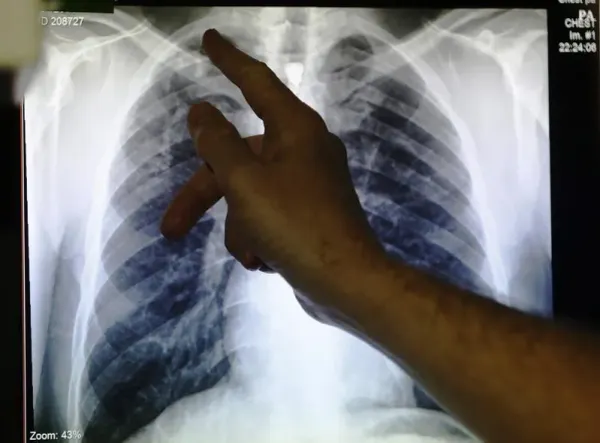

புத்ராஜெயா, பிப்ரவரி 21-பிப்ரவரி 8 முதல் 14 வரை (தொற்றுநோயியல் வாரம் 6) நாடு முழுவதும் 596 புதிய காசநோய் (காசநோய்) வழக்குகள் பதிவாகியுள்ளன, இந்த ஆண்டு மொத்த எண்ணிக்கை 3,161 ஆக உள்ளது.சுகாதார அமைச்சகம் இன்று வெளியிட்ட அறிக்கையில், சபாவில் அதிக எண்ணிக்கையிலான வழக்குகள் 755 ஆகவும், அதைத் தொடர்ந்து சிலாங்கூர் (596), சரவாக் (332) ஜோகூர் (280) கோலாலம்பூர் மற்றும் புத்ராஜெயா (244) கெடா (181) பினாங்கு (172) பேராக் (154)கிளாந்தான் (121) பகாங் (103)திராங்கானு (74) நெகிரி செம்பிலன் (62) மலாக்கா (48) பெர்லிஸ் (21) மற்றும் லாபுவான் (18)